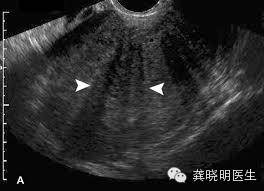

子宫肌腺症若是通过超声检查,往往能够发现子宫壁增厚,出现结构紊乱。

肌腺症在子宫内部若是局部形成一个象肌瘤一样的结节,在超声上可能会比较局限,看起来象是一个肌瘤,但是通常边界不如肌瘤清楚,绝大多数超声认为的腺肌瘤其实都是腺肌症的表现,这在核磁共振检查上更清晰。